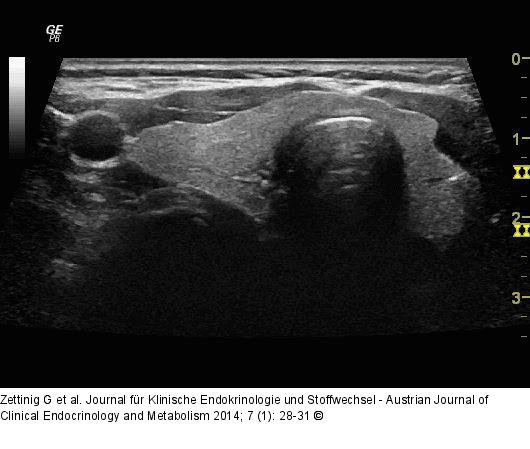

Abbildung 9: Video 1 - Rechter Lappen Rechter Lappen im Querschnitt von kaudal nach kranial und wieder zurück. |

Rechter Lappen im Querschnitt von kaudal nach kranial und wieder zurück. |